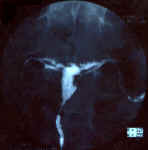

| Utérus cloisonné avec un grand septum, large dans sa partie fundique et long, s'étendant jusqu'à l'isthme utérin. Ce septum mesure environ 5 cm de longueur pour 5 mm d'épaisseur. L'isthme s'en trouve élargi, mesurant 11 mm de face. Les deux hémicavités secondaires sont de petite taille, mais avec des contours lisses et réguliers, sans aucune image d'addition ni de soustraction. L'angle entre les deux hémicavités est d'environ 600, confirmant le diagnostic d'utérus cloisonné.

Les deux trompes sont perméables, légère stagnation du contraste dans les deux ampoules, plus marquée à gauche.

Conclusion:

Utérus cloisonné avec un septum de grande taille s'étendant jusqu'au niveau de l'isthmeTrompes perméables, stagnation de contraste dans les ampoules, plus marquée du côté gauche |    |